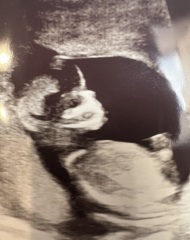

Naj08 · 04/07/2025 20:01

Is the nose bone visible in this scan? I feel like something is off with the shape and features or is that just the scan?